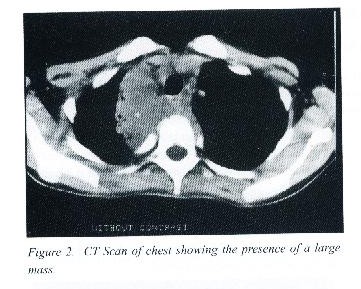

A 11 year old Bahraini girl presented with fever, generalised weakness and body aches.  Physical examination revealed a febrile, pale asthenic girl, not in respiratory distress, with diminished air entry on the right side of the chest and bronchial breathing. No lymphadenopathy or hepatosplenemegaly was detected. Laboratory  investigations revealed the Hemoglobin of 8 g/dl, platelets 827 x 109/L, white blood cells 21.3 x 10 9/L (polymorph 66%, Lymphocytes 25%).  ESR was 115 mm in 1 hr, chest radiograph (Fig 1)  showed a mass in the anterior mediastinum.  CT scan of chest  confirmed the presence of a large mass in the upper mediastinum extending anterio-posteriorly to the paravertebral region (Fig 2).  Tuberculin cold agglutination tests were negative.  Fine needle aspiration revealed the presence of non-specific inflammatory lesion.  Thoractomy was done which demonstrated a vascular mass extending from the posterior to anterior mediastinum.  Biopsy  demonstrated the presence of colonies of fungi surrounded by neutrophils which are combined with the actinomycosis laying over vascular malformation.  Patient was treated with intravenous penicillin G 200,000 unit / kg/day until the sedimentation rate returned to normal.